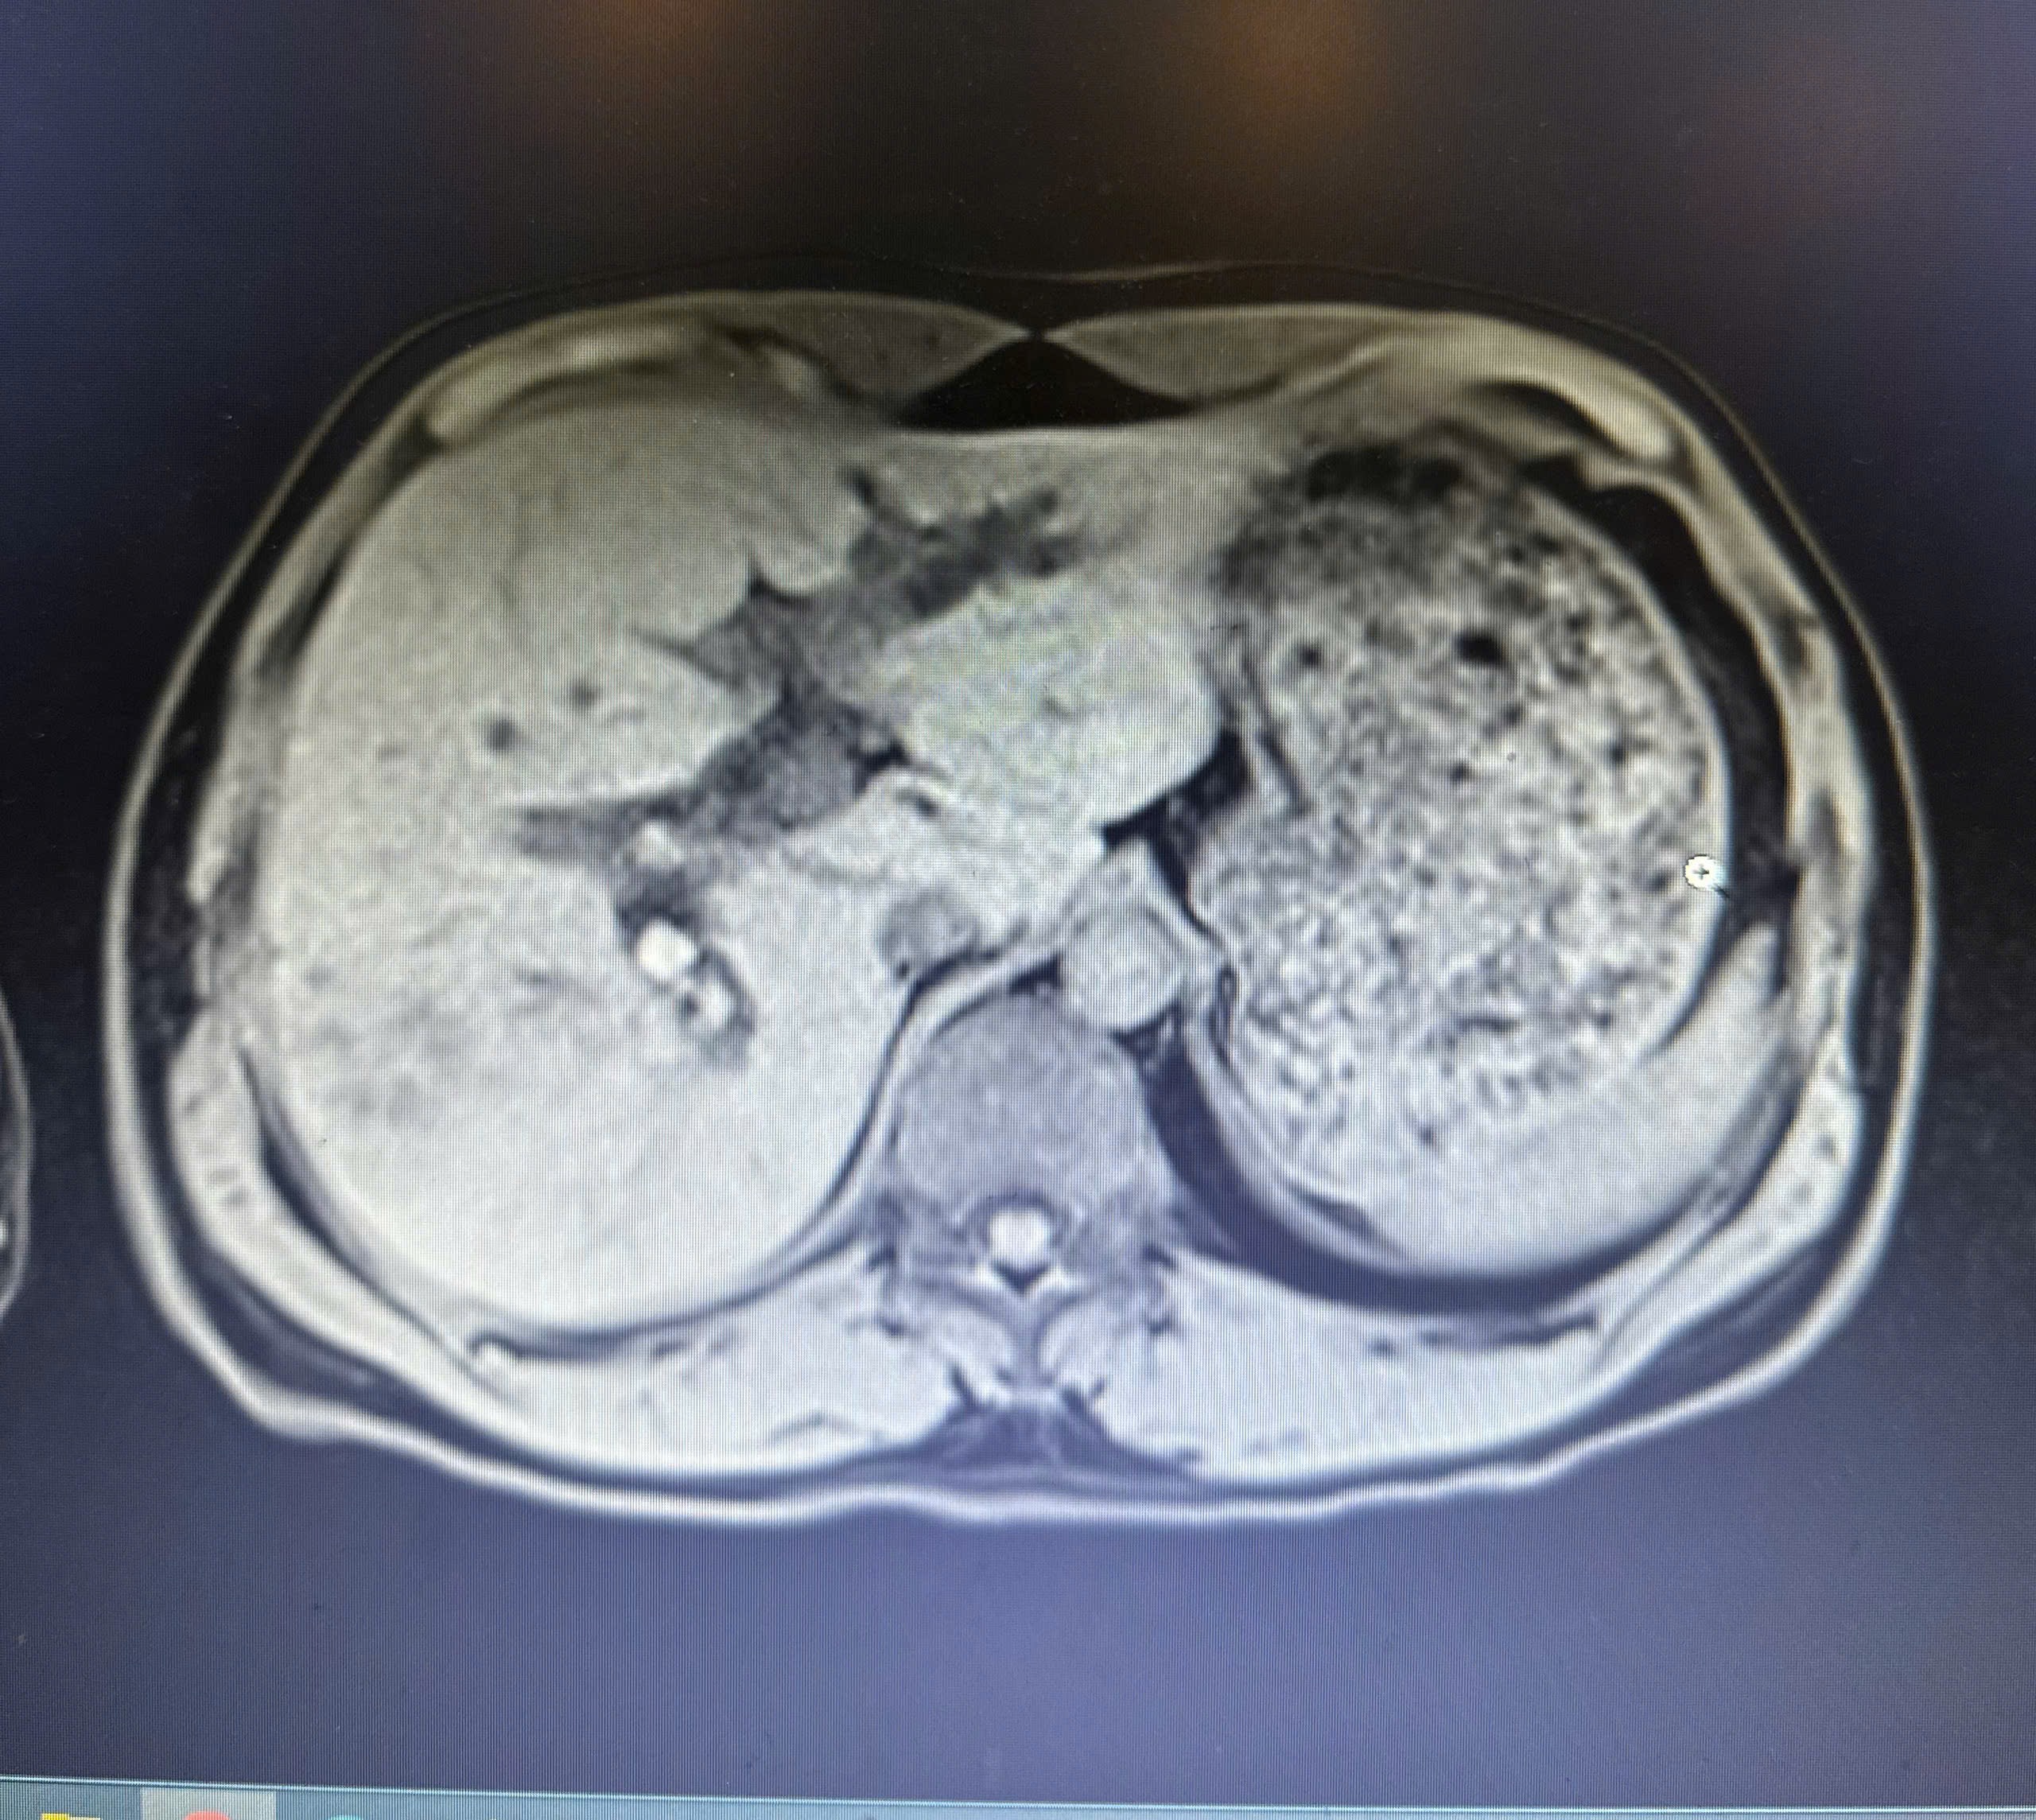

Người bệnh nhập viện trong tình trạng đau bụng kéo dài. Qua thăm khám lâm sàng và thực hiện các xét nghiệm cần thiết, đặc biệt là chụp cộng hưởng từ gan mật (MRI), các bác sĩ phát hiện hệ thống đường mật trong gan hai bên giãn. Đường mật gan phải có nhiều sỏi xếp chuỗi, viên lớn nhất kích thước khoảng 16 x 15 mm; ống mật chủ giãn 14 mm, chứa hai viên sỏi kích thước khoảng 15 mm.

Hình ảnh chụp cộng hưởng từ (MRI) cho thấy hình ảnh sỏi trong gan xếp chuỗi rất rõ (màu trắng)